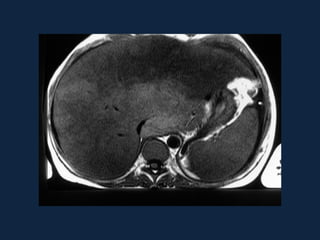

CONGESTÃO HEPÁTICA

• Insuficiência cardíaca levando a

estase na VCI e dificuldade de

drenagem das veias hepáticas.

• Hepatomegalia, dilatação da VCI

e das veias hepáticas.

• Aspecto “em mosaico” do

parênquima hepático que se

homogeniza tardiamente.

• Ascite.

• Halo periportal.

Distribuição perivascular

• Esquistossomose

– Fibrose periportal

– Hipertensão pré-sinusoidal

– US: Aumento da ecogenicidade

periportal (“céu estrelado”)

– TC:

• SC: Bandas hipodensas

periportais

• CC: contrastação tardia

– RNM:

• T1: Bandas fibrosas 

• T2: Bandas fibrosas 

• Contraste tardio

ESQUISTOSSOMOSE MANSÔNICA

• Intensa reação

inflamatória que

resulta em fibrose

periportal.

• Atrofia do lobo direito,

hipertrofia do lobo

esquerdo e

hipertensão portal.